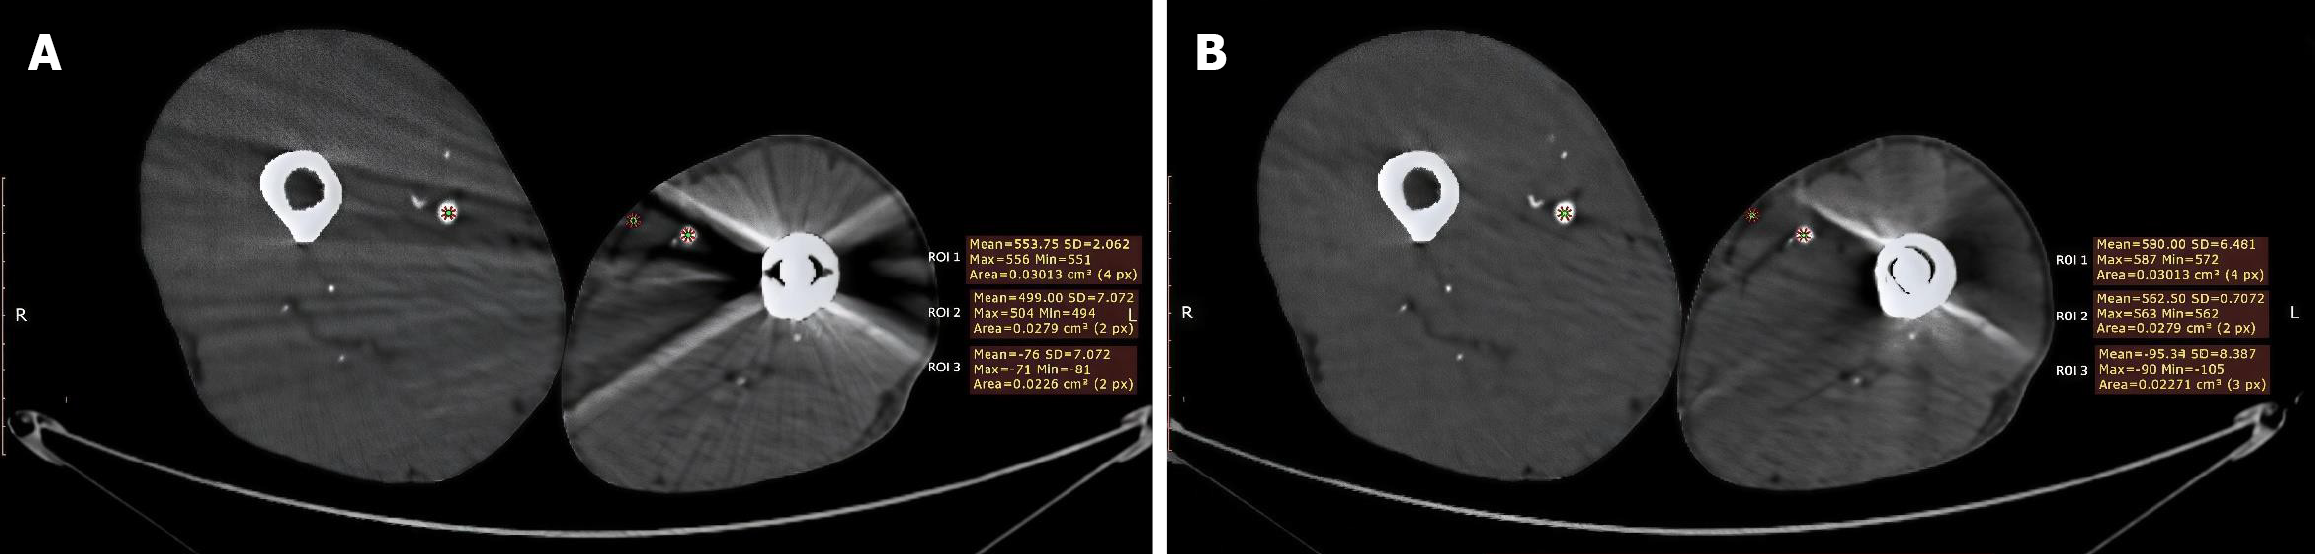

Case 1: 42-year-old male with left femoral fracture treated with medullary nail fixation. CTA assessment to evaluate lower limb vasculature was requested as pre-operative workup for knee arthroplasty (Figure 1).

Figure 1

Figure 1 Improved femoral artery visualization after metal artifact reduction software processing. A: Pre-metal artifact reduction (MAR), lower limbs axial computed tomography angiography without MAR software demonstrates streak and bloom artifacts originating from left femoral intra-medullary nail. Three regions of interest (ROI) were placed; ROI 1 in the contralateral (right) femoral artery shows mean Hounsfield unit (HU) of 553.75, SD = 2.062, ROI 2 in the ipsilateral (left) femoral artery demonstrates suboptimal contrast opacification, mean HU of 499.0, SD = 7.072. ROI 3 was placed in left subcutaneous fat with mean HU of -76, SD = 7.072; B: Post-MAR, same anatomic level post MAR software processing demonstrates marked artifact reduction with improved visualization of femoral artery. ROI 1 in the contralateral (right) femoral artery shows mean HU of 580.0, SD = 6.481, ROI 2 in the ipsilateral (left) femoral artery demonstrates suboptimal contrast opacification, mean HU of 562.5.0, SD = 7.072. ROI 3 was placed in left subcutaneous fat with mean HU of -95.3, SD = 8.387. ROI: Regions of interest.